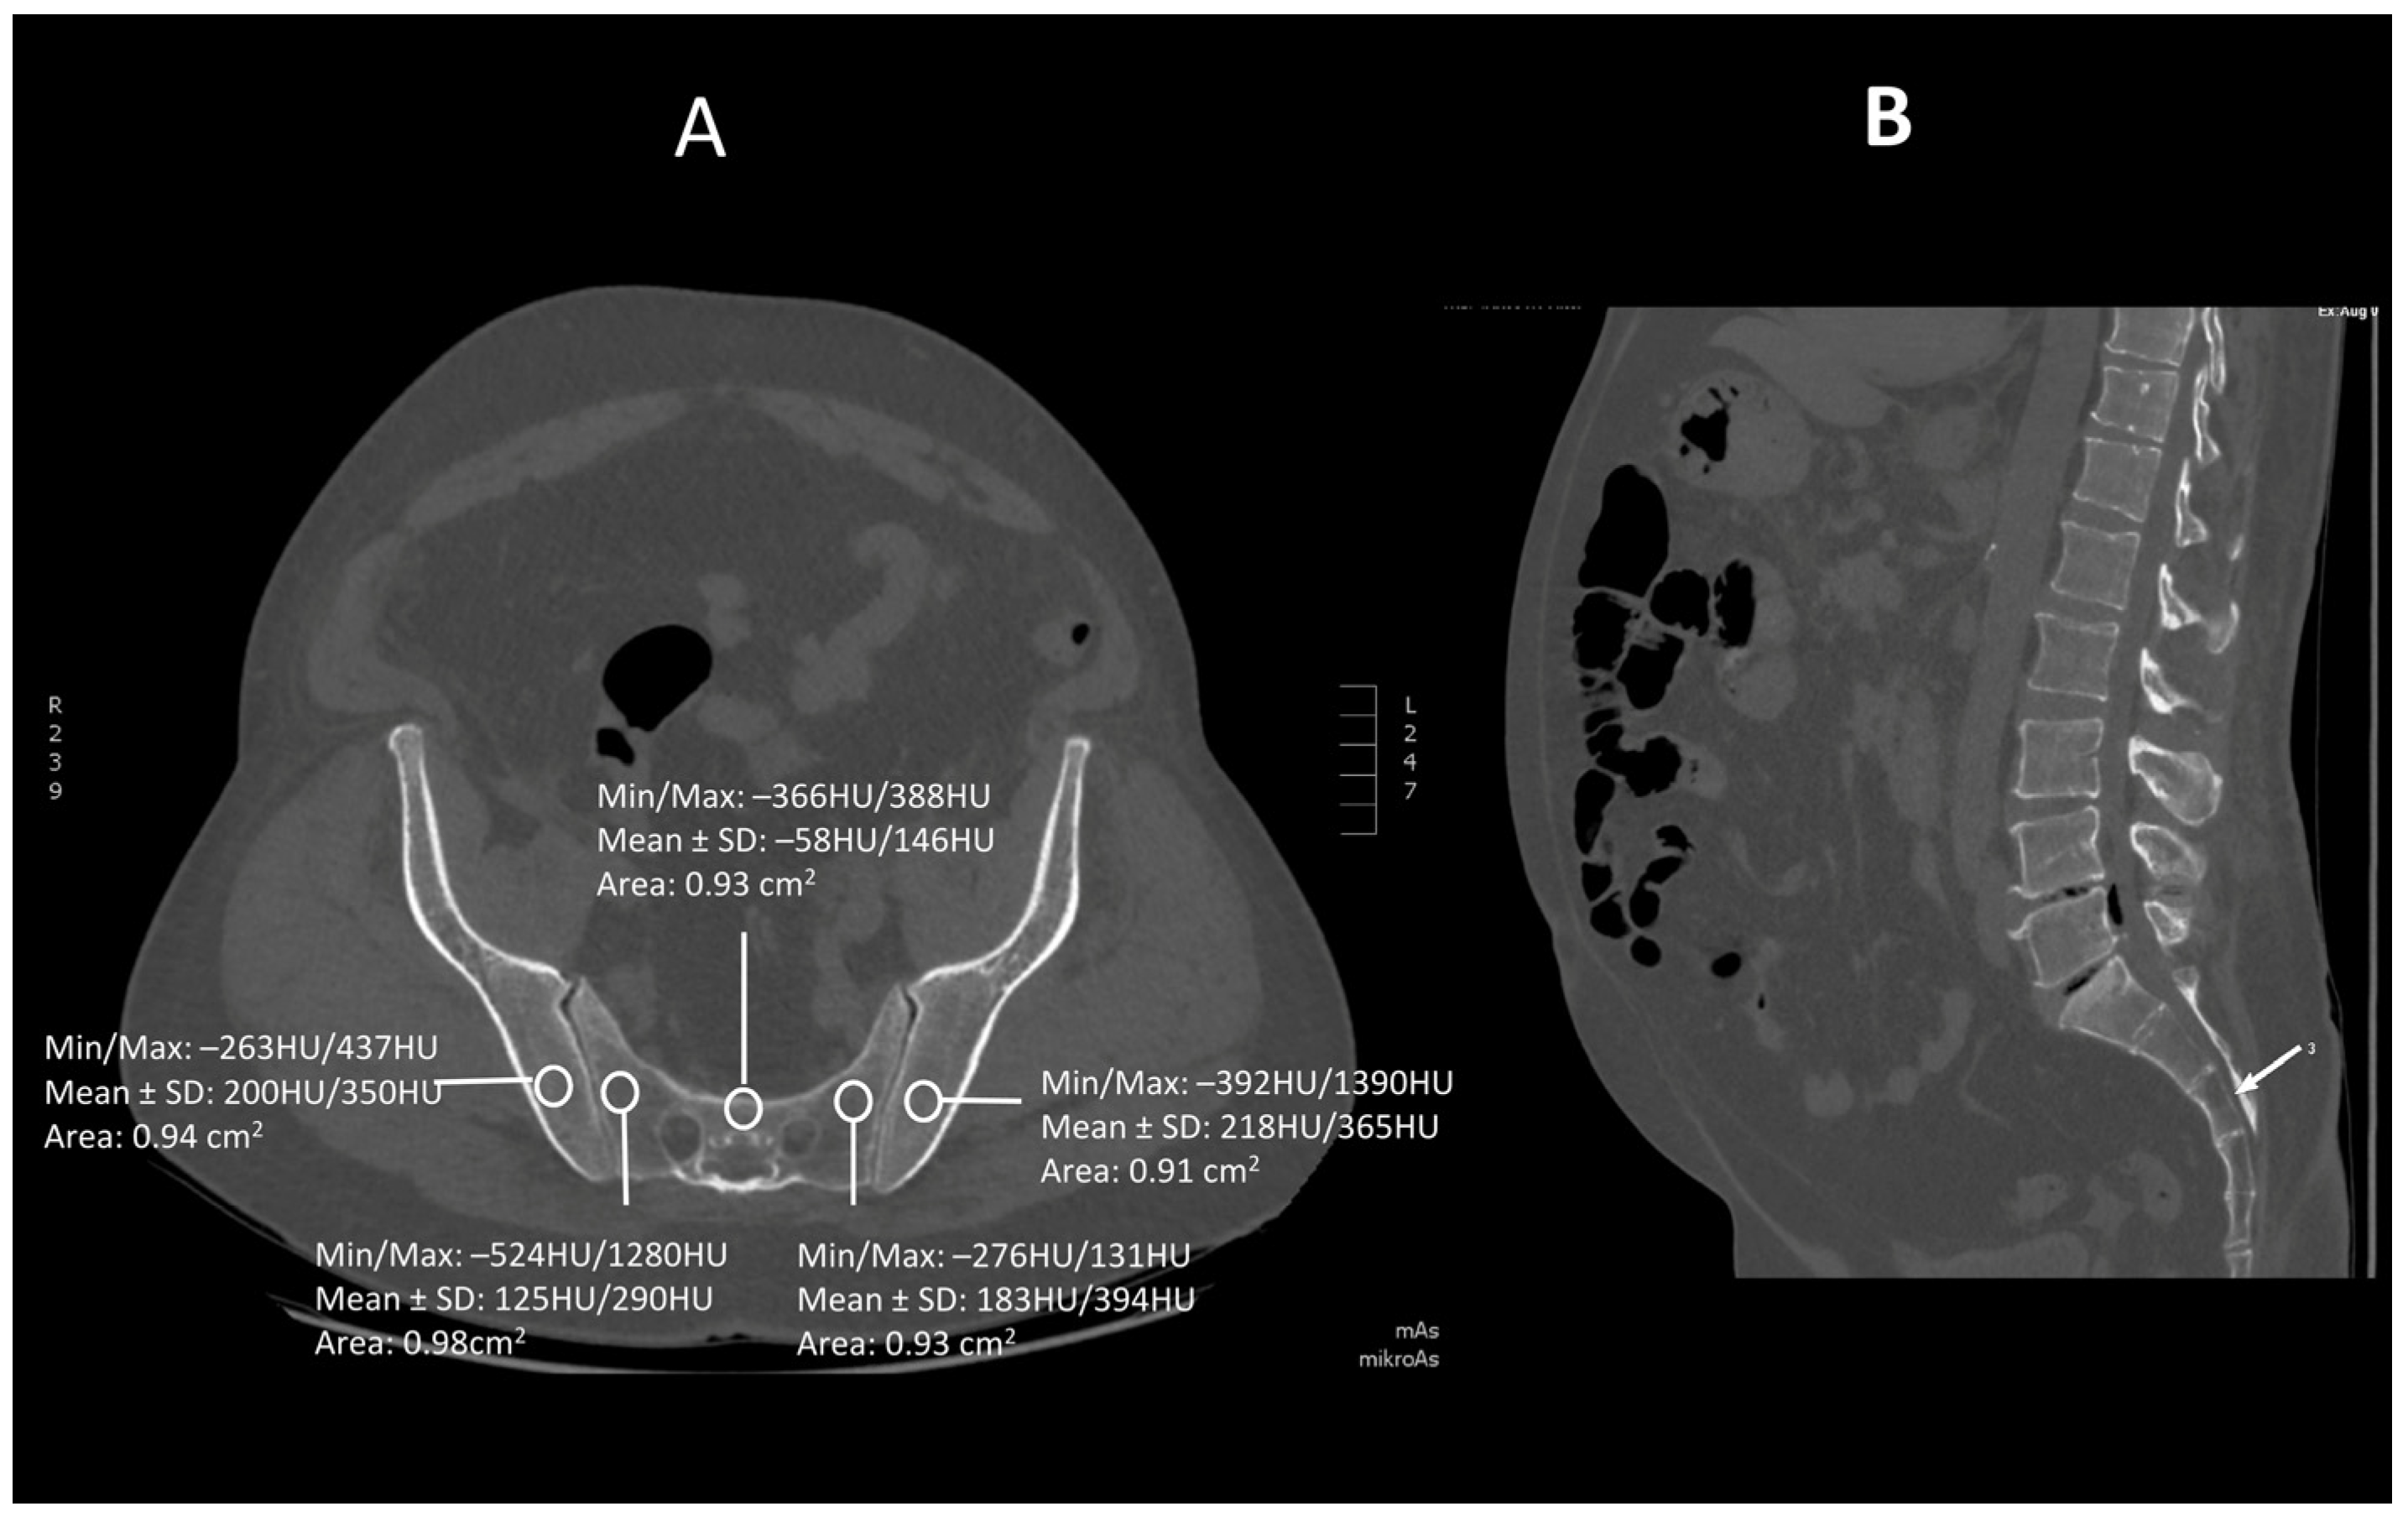

2.2. Technique Procedures